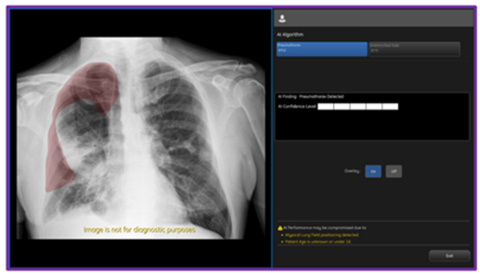

CHICAGO--(BUSINESS WIRE)--Today GE HealthCare (Nasdaq: GEHC) announced an industry-first US FDA 510K clearance of Critical Care Suite 2.1 featuring a Pneumothorax (PTX) algorithm for the detection, notification, triage and diagnosis of PTX. The updated PTX algorithm expands Critical Care Suite’s on-device triage capabilities by providing immediate notification of the presence or absence of pneumothorax, as well as an overlay display both on-device and in PACS to assist with PTX localization.

With this latest update, Critical Care Suite 2.1 provides immediate on-device detection and triage notifications for the presence or absence of pneumothorax (PTX). When a PTX is detected, an overlay is displayed in the area where the PTX was located both on-device as well as in PACS to assist with PTX localization, as well as improve speed and accuracy of PTX diagnosis. By hosting Critical Care Suite on-device, critical insights are available at the point of care and across the entire clinical care team.

The algorithm operates with a high degree of accuracy – partially localizing 100% of all detected large PTXs and 96% of all detected small PTXs, while limiting false alerts (94% specificity).7